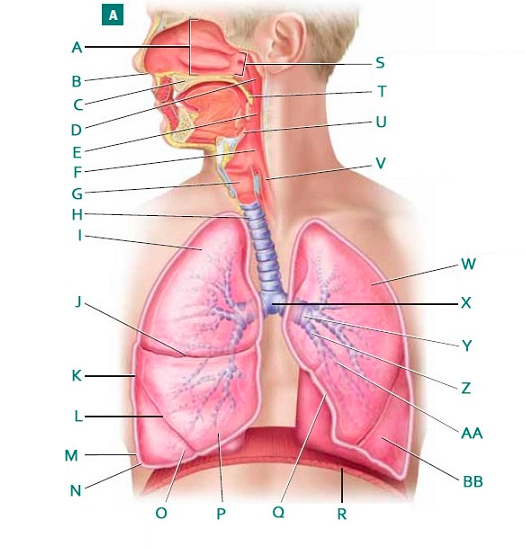

Alveolus/alveoli

Bronchioles

C-Rings (=tracheal cartilage)

Epiglottis

Esophagus

Hard/soft palate

Horizontal fissure (of right lung)

Inferior/middle/superior concha (s.) conchae (pl.)

Larynx

Left/right oblique fissue (of lung)

Left/right primary bronchus/bronchi

Nares

Nasal Cavity

Nasal septum

Naso/oro/laryngo-phraynx

Oral Cavity

Paranasal sinuses

Pleural cavity

Pleural membrane

Secondary bronchi

Trachae

Upper/middle/lower lobe (of lung)

Uvula

Vestibule (of nasal cavity)

Vocal folds (=vocal cords)